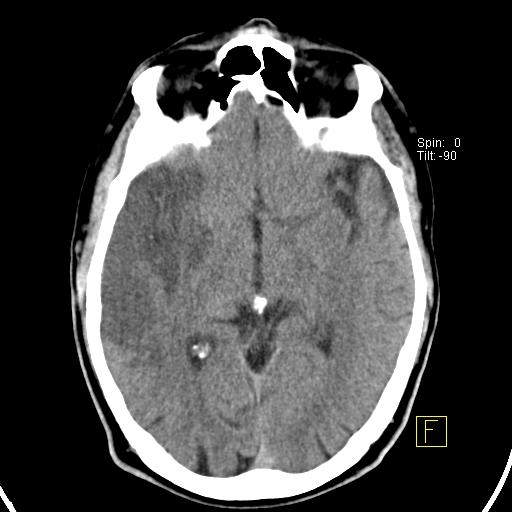

Внутричерепная гипотензия: КТ-исследования и их интерпретация